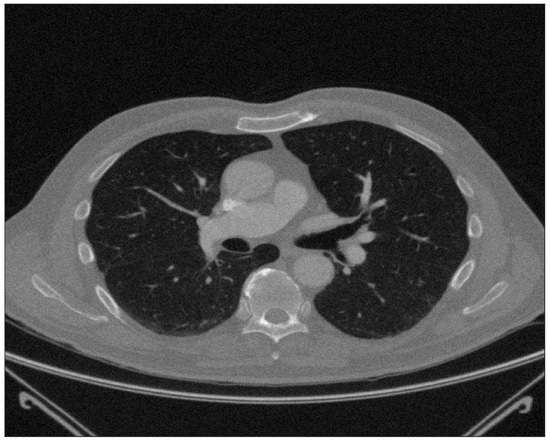

In the era of rapid development of machine learning and pattern recognition, some image recognition technologies are applied in the medical field. For example, through the processing of lung CT images, we can identify whether the lung has a disease. The following two methods are often used to quantitatively evaluate the severity of emphysema: one is CT density measurement. Based on the pixel image of CT digital, calculate the average lung density of the patient, then establish the threshold, calculate the proportion of the area below the threshold, and evaluate the situation of emphysema. The other is the percentile density measurement (PD) technique. Analyze the attenuation distribution curve of lung density, give a percentile (commonly 5% and 95%), calculate the area below the percentile density curve, and evaluate the symptoms of emphysema [28]. In this section, we shall apply our proposed method to analyze the lung CT image dataset downloaded from Kaggle, which can segment lungs accurately.

There is a picture of a subject in Appendix C Figure A1. Among them, we regard 5% and 95% PD data as the corresponding continuous response variable, respectively. For smokers, these values are usually high, indicating that other substances in the lungs have accumulated. The data include 267 instances and 512*512 continuous covariates stretched by picture pixels.

By giving different values of quantile grid points K = 2 , 3 , , 6 and considering the threshold of FDR under the given prespecified level α = 0.05 , we obtain the different segmentations and extractions. The numbers of selected picture pixels are displayed in Table 4. It is clear that QCS-FDR loses efficacy, and QA-SVS-AFD works when K 3 . Fortunately, QA-SVS-FDR works effectively under all values of K = 2 , 3 , , 6 . Compared with the QA-SVS-AFD(K) and the QA-SVS-FDR(K), under the hypothesis testing (2), it could be found that the screened active variable set is estimated by the rejection region of the QA-SVS-AFD(K) path, which controls the probability around 1 / ( 512 512 ) with not enough number of active variables. The QA-SVS-FDR(K) selects the active variable sufficiently by testing the null hypothesis of testing (2) under the given prespecified FDR level α = 0.5 . We illustrate the extraction by plotting the segmented lung CT with the average of the values of the selected predictors, which are presented in Appendix C, Figure A2, Figure A3, Figure A4, Figure A5 and Figure A6. These results may provide some information for measuring important clinical parameters (lung volume, PD, etc); considering the length of this paper, we do not go further.